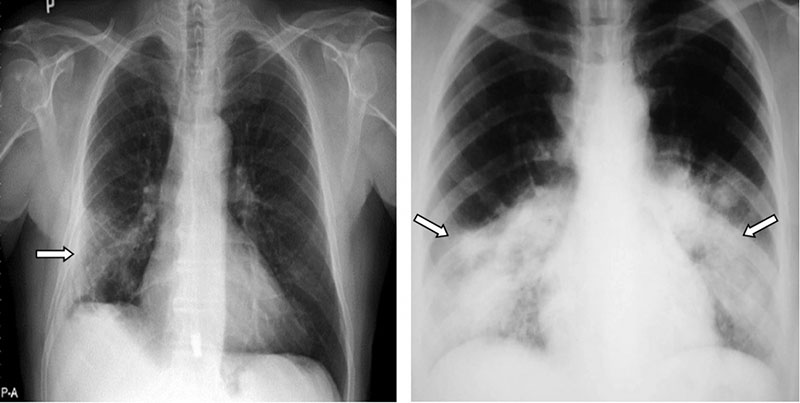

Xơ phổi là hậu quả của các tổn thương phổi trong giai đoạn mắc Covid cấp tính khiến nhu mô phổi bị phá hủy, dày lên, xơ hóa, cứng lại vì mất đi tính đàn hồi và giảm chức năng hô hấp, làm phổi giãn nở kém, khó hoạt động trở lại bình thường.

Những tổn thương, xơ hóa làm giảm khả năng đàn hồi của phổi. Điều này dẫn đến tình trạng thiếu oxy của cơ thể. Các triệu chứng ban đầu của xơ phổi hậu Covid thường biểu hiện ở mức độ tương đối nhẹ. Tuy nhiên, các triệu chứng của bệnh có thể kéo dài và xuất hiện rõ ràng hơn nếu người mắc không áp dụng biện pháp điều trị phù hợp.